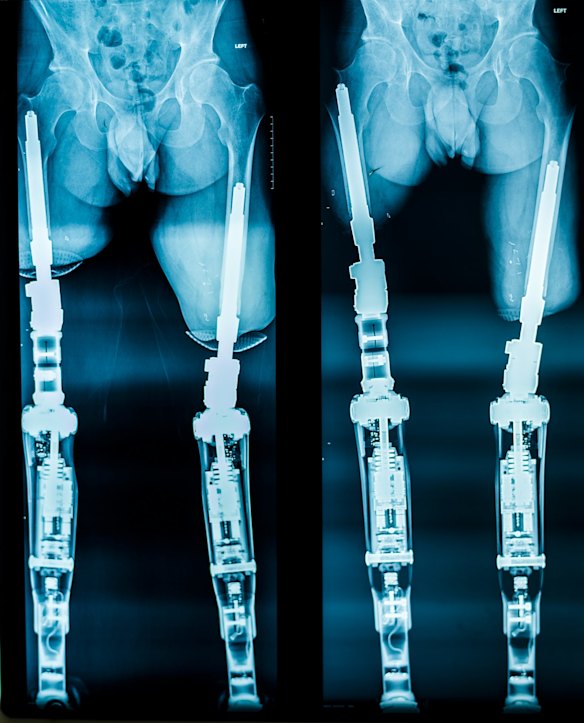

Behind the scenes: X-rays demonstrating osseointegration.Tim Bauer

At Muderis's clinic at the Norwest Private Hospital in Bella Vista, in north-west Sydney, three amputees are sharing stories about life since their operations. They've undergone a procedure called osseointegration - a titanium rod is inserted into their femur, into which a prosthesis seamlessly clicks, giving them a greater range of movement, and far less discomfort, than a traditional "socket" prosthesis. One young woman, Miranda Cashin, who was born without a tibia in her right leg, is tearfully describing how the operation has radically changed her life. After years of struggling with a socket prosthesis, and falling back on crutches and a wheelchair to get about painlessly, Miranda now goes on five-kilometre walks.

Thanks to Muderis's pioneering work on prosthetics, and patents on titanium devices he has designed, Australia is now at the forefront of osseointegration technology. "What makes me do this," he says, "is that I came from a war-torn region where people regularly lost limbs. For some, this is worse than dying, because it changes their lives so fundamentally; there's the fear of being dependent on others. Eight of our patients, after being on Centrelink payments for years, are now working full-time and paying tax."